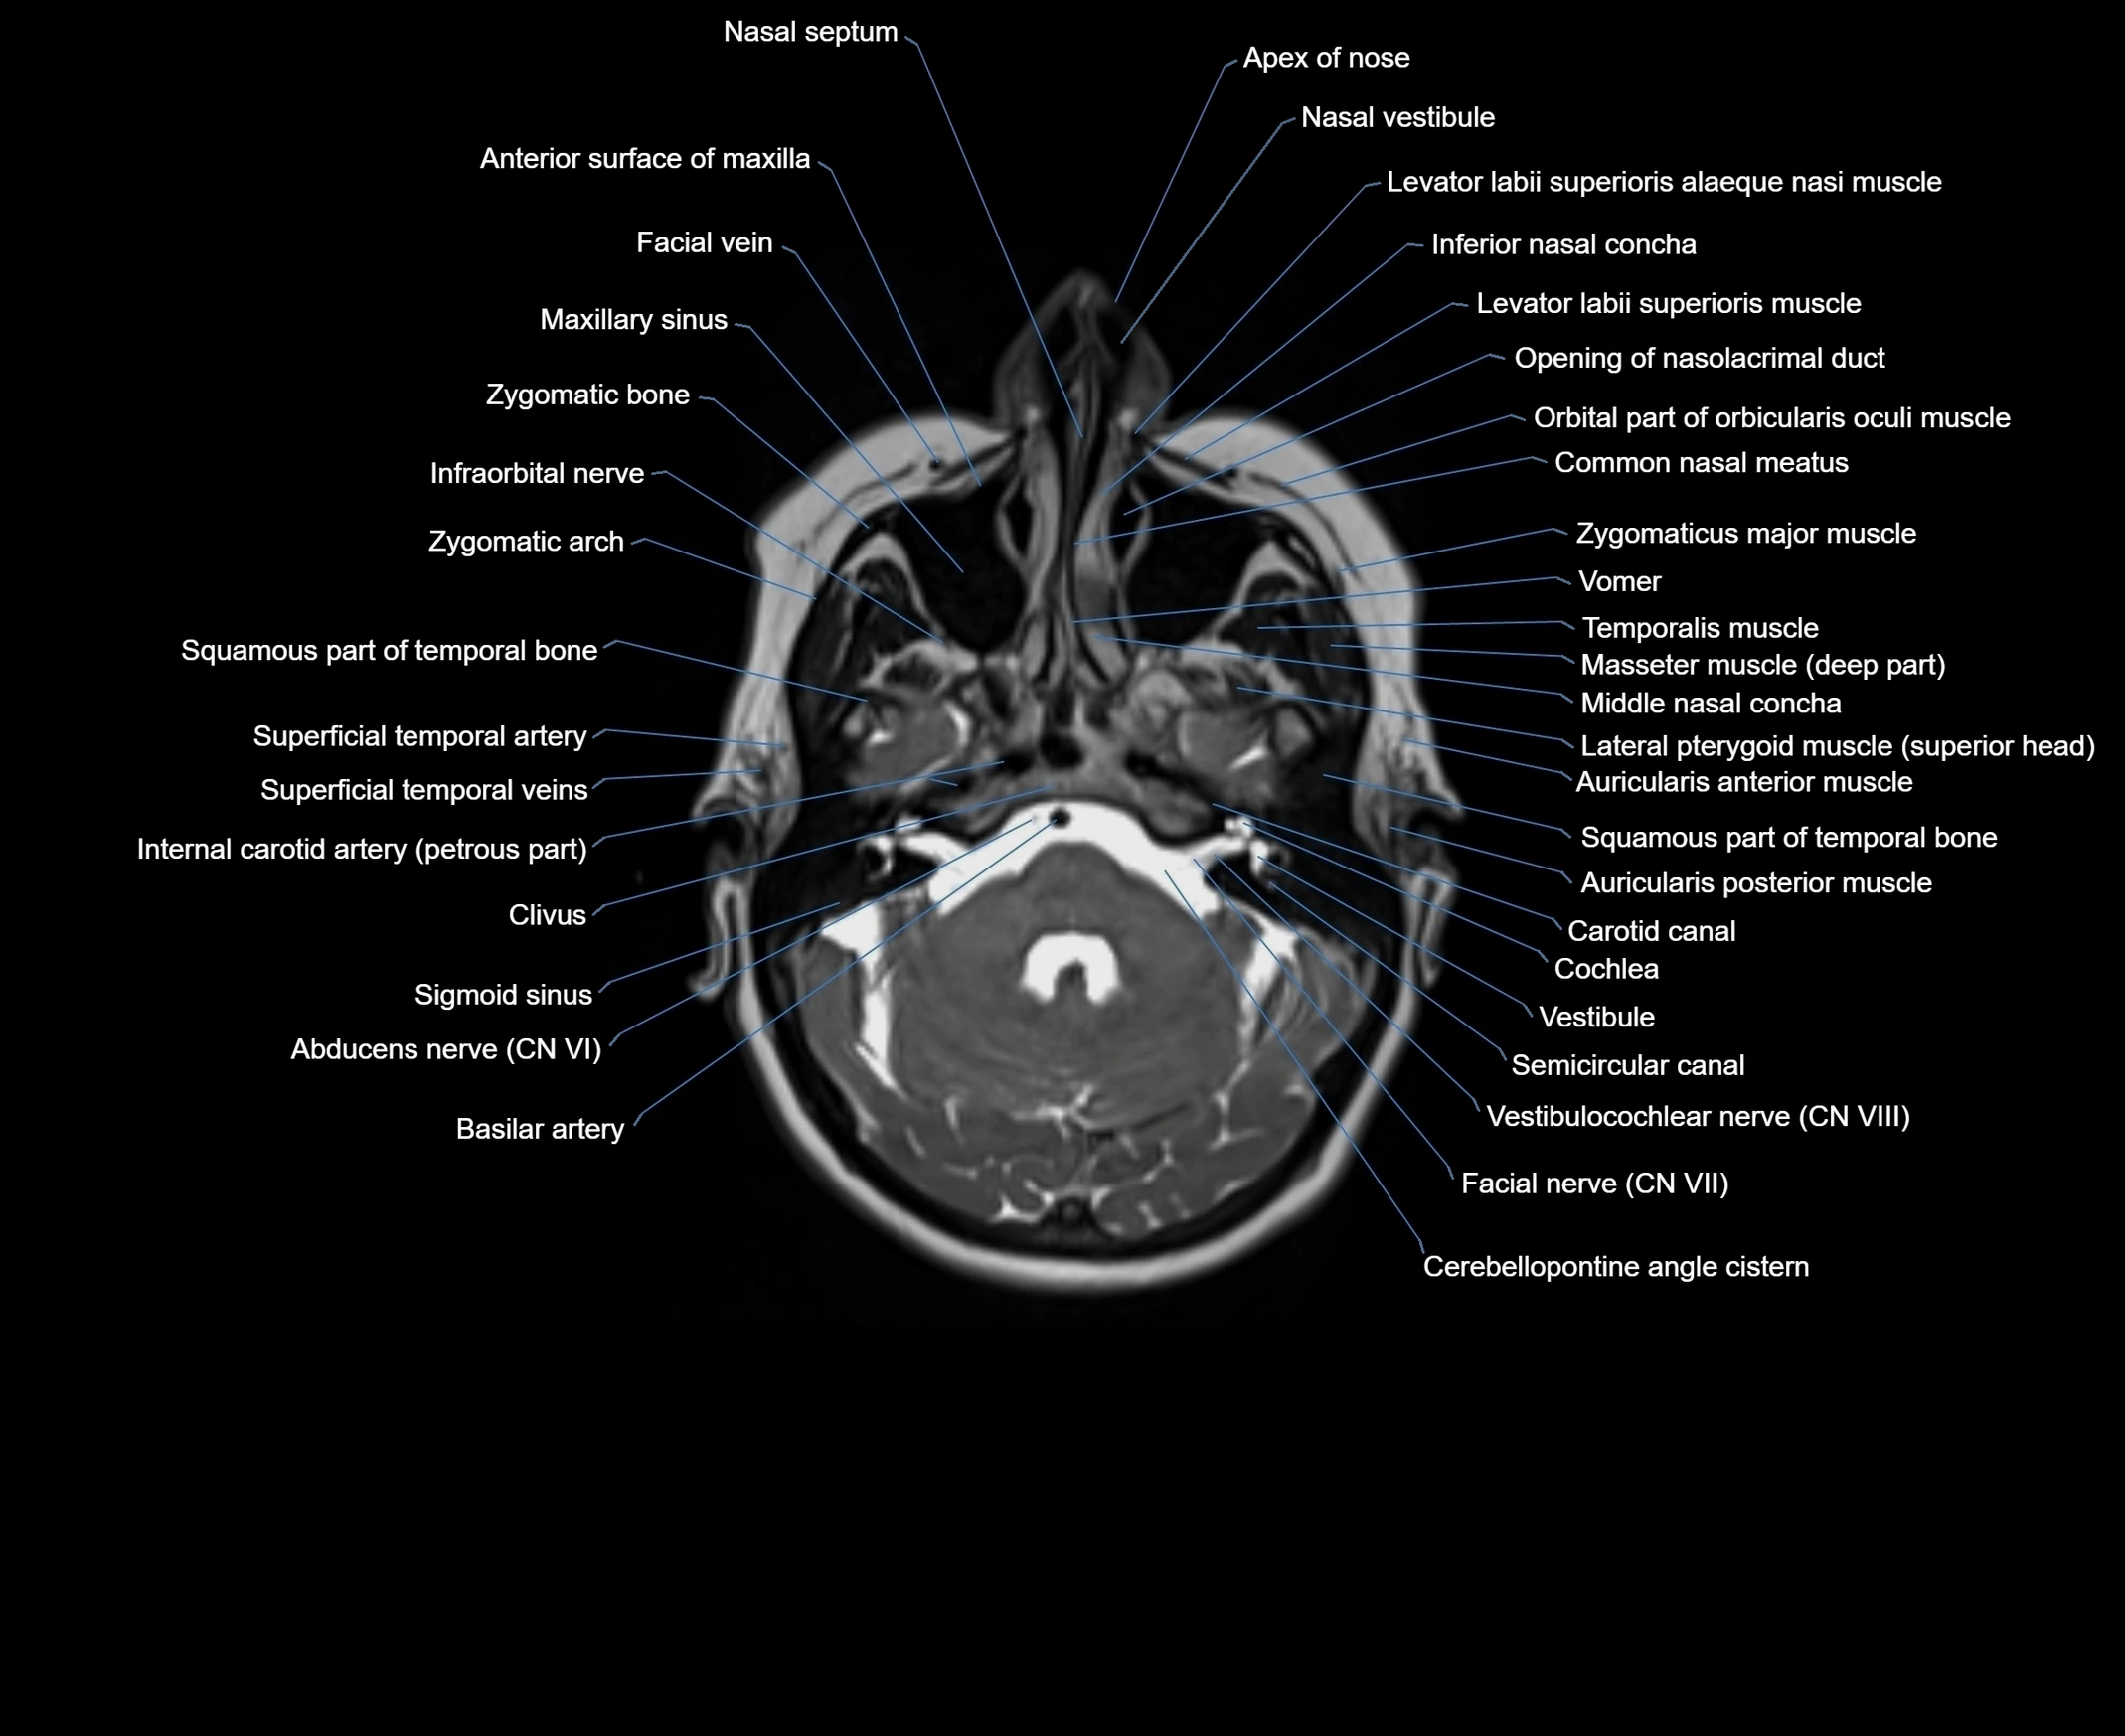

MRI images